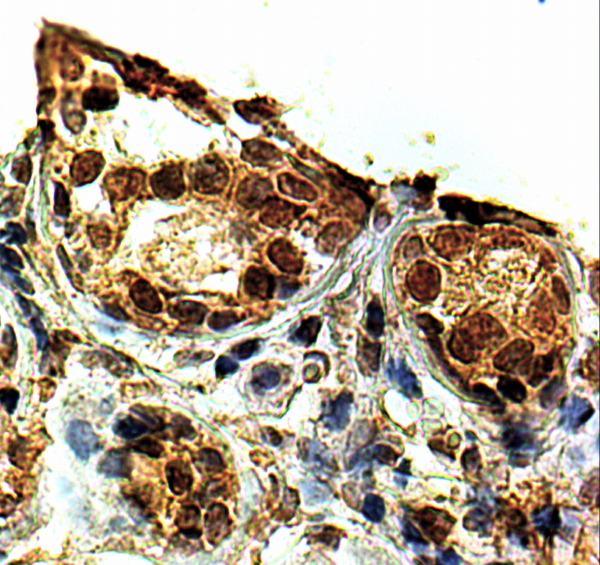

APG00176G (2 μg/ml) staining of paraffin embedded Human Breast. Steamed antigen retrieval with citrate buffer pH 9, HRP-staining. |